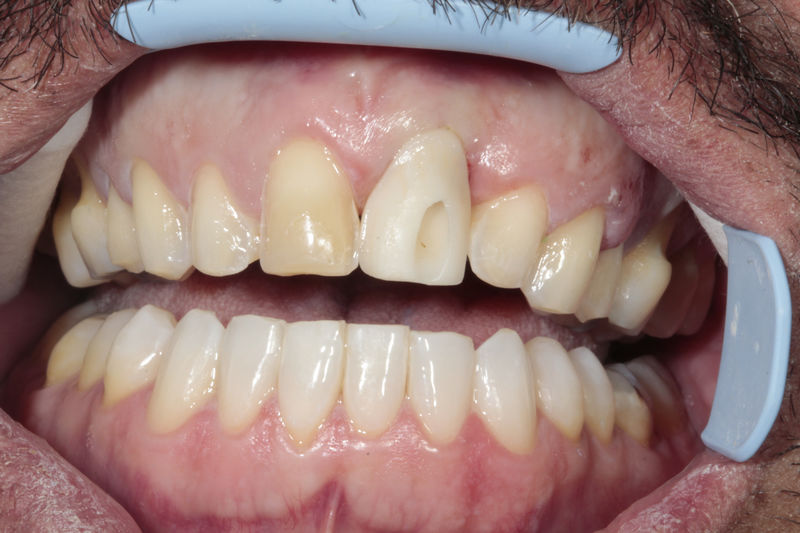

Ortodoncia y coronas.